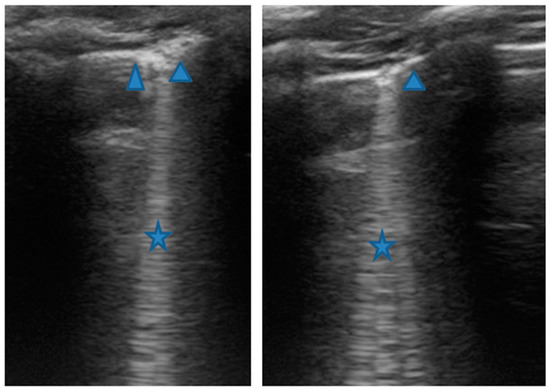

LUS was also performed, which showed a picture compatible with the features detected on CT (Figure 9).

Figure 9.

Grayscale lung ultrasound examination shows a picture of sonographic interstitial syndrome (SIS) represented by: (A): irregularity of the pleural line, short vertical artifacts, and long vertical artifacts unevenly distributed bilaterally; (B,C): irregularity of the pleural line, sub-centimeter consolidations associated with long confluent vertical artifacts located mainly in the right lung fields, mainly in the mid-apical area; (D,E): short vertical artifacts with pleural line irregularities unevenly distributed bilaterally.

Furthermore, evaluating some patients who had important ultrasound lesions (such as atelectasis of a certain entity, or diffuse sonographic interstitial syndrome), as in the first three cases, we wondered if some of these lesions may have already been present before the acute attack, and also in consideration of the finding of a positive ultrasound picture even in the stability phase, and after starting an adequate preventive therapy. Hence, there is a need to take into account the asthmatic phenotype and its severity for all patients, and also to evaluate the ultrasound patterns of patients in the stability phase in an outpatient setting, as in case 6. In the latter case—a patient with allergic asthma severe eosinophilic atopic type 2, but in a stability phase—the chest CT (Figure 8) showed signs of airway and lung parenchyma remodeling compatible with the patient’s severe clinical picture. LUS (Figure 9) showed a picture of diffuse short vertical artifacts, long confluent and non-confluent artifacts, and irregularities of the pleural line and sub-centimeter consolidations: lesions that, in the absence of acute respiratory pathology (as in our case), could be compatible with the remodeling pattern found on the chest CT.